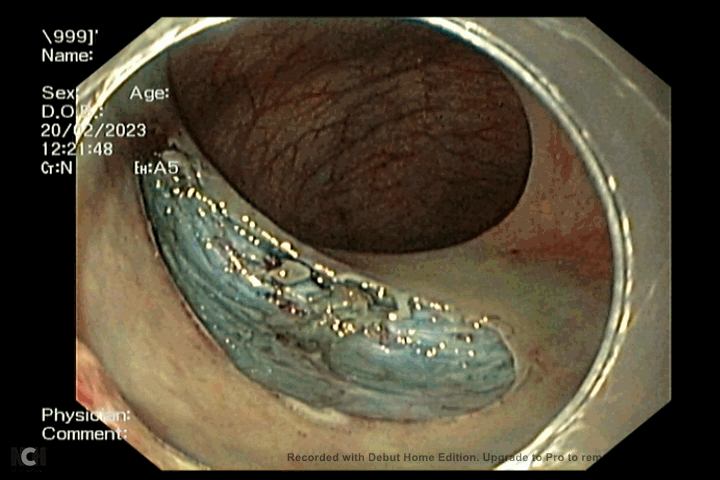

Chị V. sau đó được các bác sĩ cắt khối u bằng kỹ thuật phẫu tích dưới niêm mạc qua nội soi (ESD). Khối u đã được cắt trọn và làm xét nghiệm giải phẫu bệnh lý. Kết quả xét nghiệm giải phẫu bệnh và hóa mô miễn dịch cho kết quả là u thần kinh nội tiết.

Khối u được cắt trọn bằng kỹ thuật ESD (Ảnh: BV Ung bướu Đà Nẵng)

Phẫu tích dưới niêm mạc qua nội soi là một kỹ thuật khó, đòi hỏi bác sĩ phải có nhiều kinh nghiệm và kỹ thuật thành thạo. ESD được chỉ định đối với các u thần kinh nội tiết và các tổn thương tiền ung thư, ung thư sớm ống  tiêu hóa. Kỹ thuật này giúp bệnh nhân được điều trị triệt để qua nội soi mà không cần phải phẫu thuật.